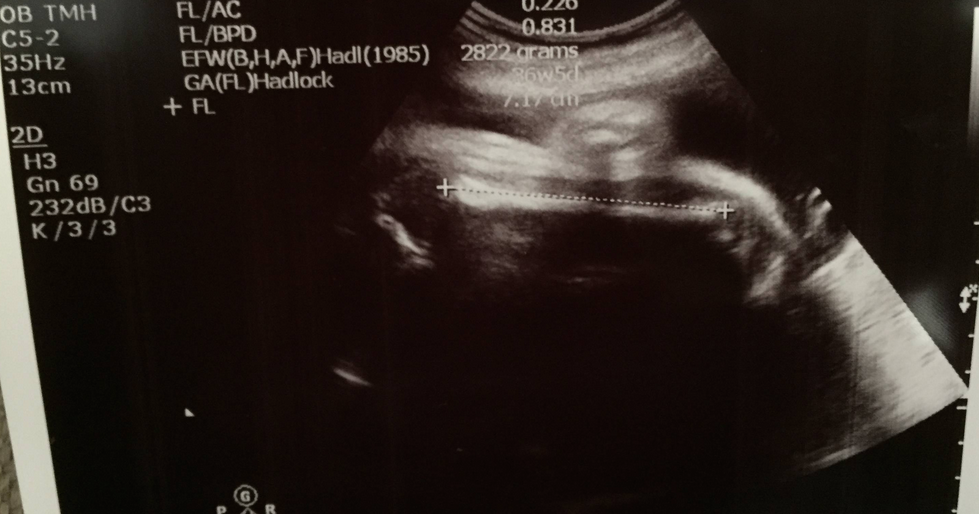

大脾骨~而家骨頭鈣化多咗令超聲波難啲穿透,加上入面又開始擁擠,難啲睇到BB呱嘅姿勢了~不過起碼知道佢乖乖頭仔向下,背脊靠我右邊,手手腳腳就堆係我左邊,當然啦,佢隨時都可以郁郁郁,呢啲左右嘅問題好快又唔係咁樣一回事了~

用咗三個parameter嚟計入算式,estimate今日2.97kg,叫做75-90 percentile,比起一個星期前嘅2.7kg重咗200幾gram都好合適丫,而今個星期中做嘅CTG又正常,咁講嘅話我唔重都冇問題丫~我係度咕嚕,我同day都唔高,BB呱又會咁大粒嘅?﹗不過其實我BB時都幾大粒,我38週出世有7磅半,按而家呢個趨勢嚟講BB呱都應該都差不多,day係早產細粒B,都唔知佢如果有機會長到足月係咪都係大隻B?﹗大隻細隻都好,健康就好~